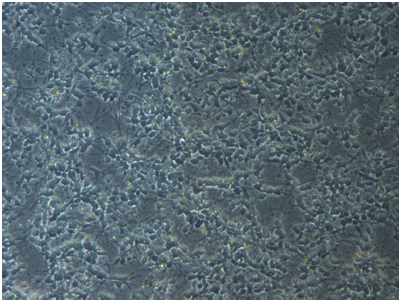

Cortical neurons extended multiple neurites per neuron with increasing neurite outgrowth over the first week in culture (Figure 1). Relative to normal group, neuron survival rates had significant changes in oxygen deprivation group, and decreased to 23.1±3.2% (n=6) Compared with oxygen deprivation group, high, middle and low concentration of NP treatment increased cell survival rate to 61.7±6.1% , 55.0±5.0% and 36.7±3.7% (n=6, Figure 2)

Figure 1 Photomicrographs of cultured cortical neurons. Cortical neurons extended multiple neurites per neuron with increasing neurite outgrowth over the first week in culture (200×).